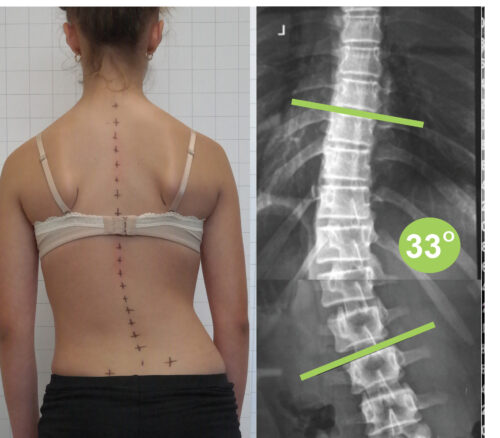

اعوجاج العمود الفقري هو انحناء غير طبيعي يحدث في الجانب، أي يمينًا أو يسارًا، وغالبًا ما يصاحبه دوران في الفقرات. لذلك، لا يكون مجرد انحناء بسيط، بل حالة ثلاثية الأبعاد تؤثر على شكل الجسم بالكامل.

غالبًا ما يظهر اعوجاج العمود الفقري خلال فترة المراهقة، خاصة مع النمو السريع بين عمر 10 إلى 16 سنة. ومع ذلك، يمكن أن يظهر في أي عمر، سواء عند الأطفال أو البالغين.

عاشرًا: متى يحتاج الطفل إلى حزام اعوجاج العمود الفقري أو حزام تقوس الظهر؟

يتم استخدام الحزام الطبي PioBrace في حالات اعوجاج العمود الفقري المتوسطة، خاصة أثناء فترة النمو.

📌 يعمل الحزام على:

- تقليل الانحناء

- توجيه نمو العمود الفقري

- تحسين استقامة الجسم

👉 ومع الالتزام، يمكن أن يقلل بشكل كبير من الحاجة إلى الجراحة.